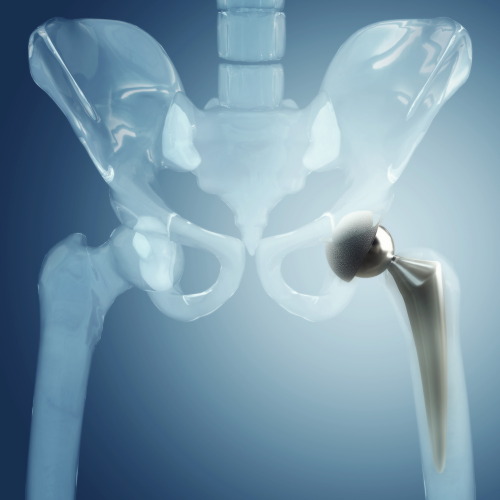

কোমড় ও হাঁটুর জোড়া প্রতিস্থাপন